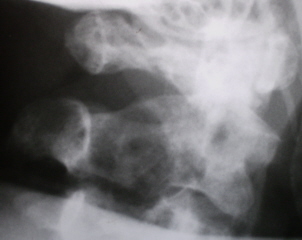

Иллюстрации 9, 10, 11. Множественные очаги деструкции костной ткани в поясничных позвонках и в крестце